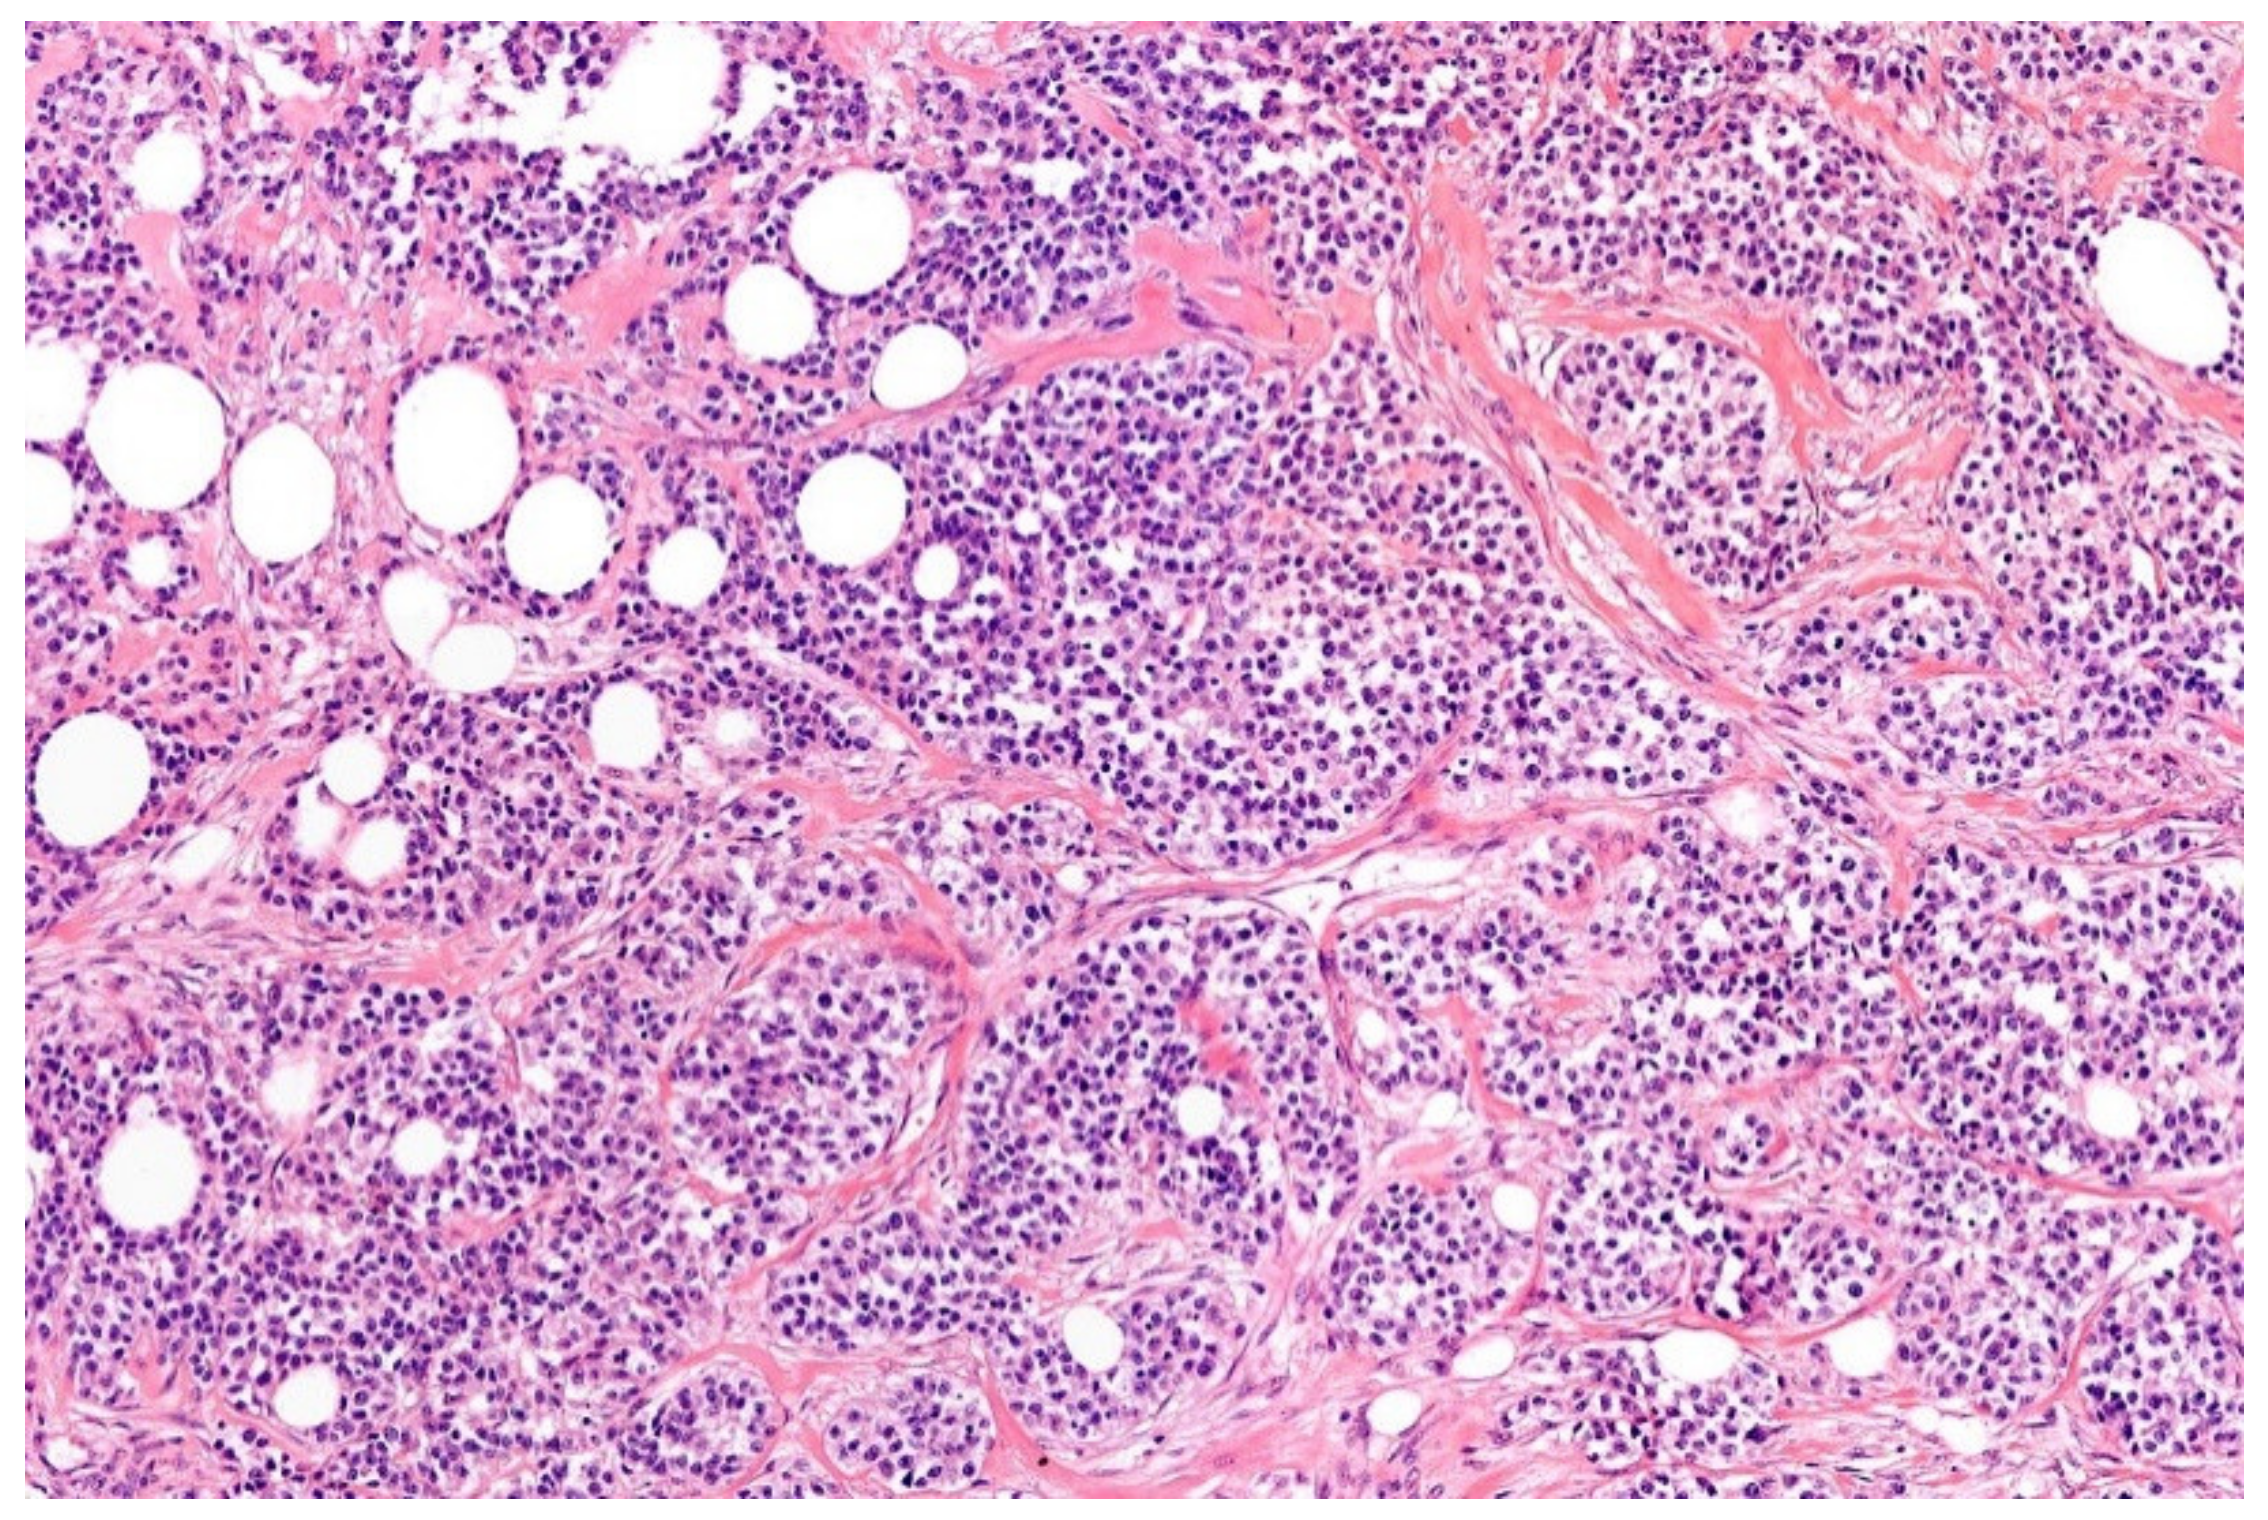

2. Ewing Sarcoma

3.1. NFATc2-Rearranged Sarcoma

3.2. EWSR1-PATZ and EWSR1-VEZF1 Rearranged Sarcoma